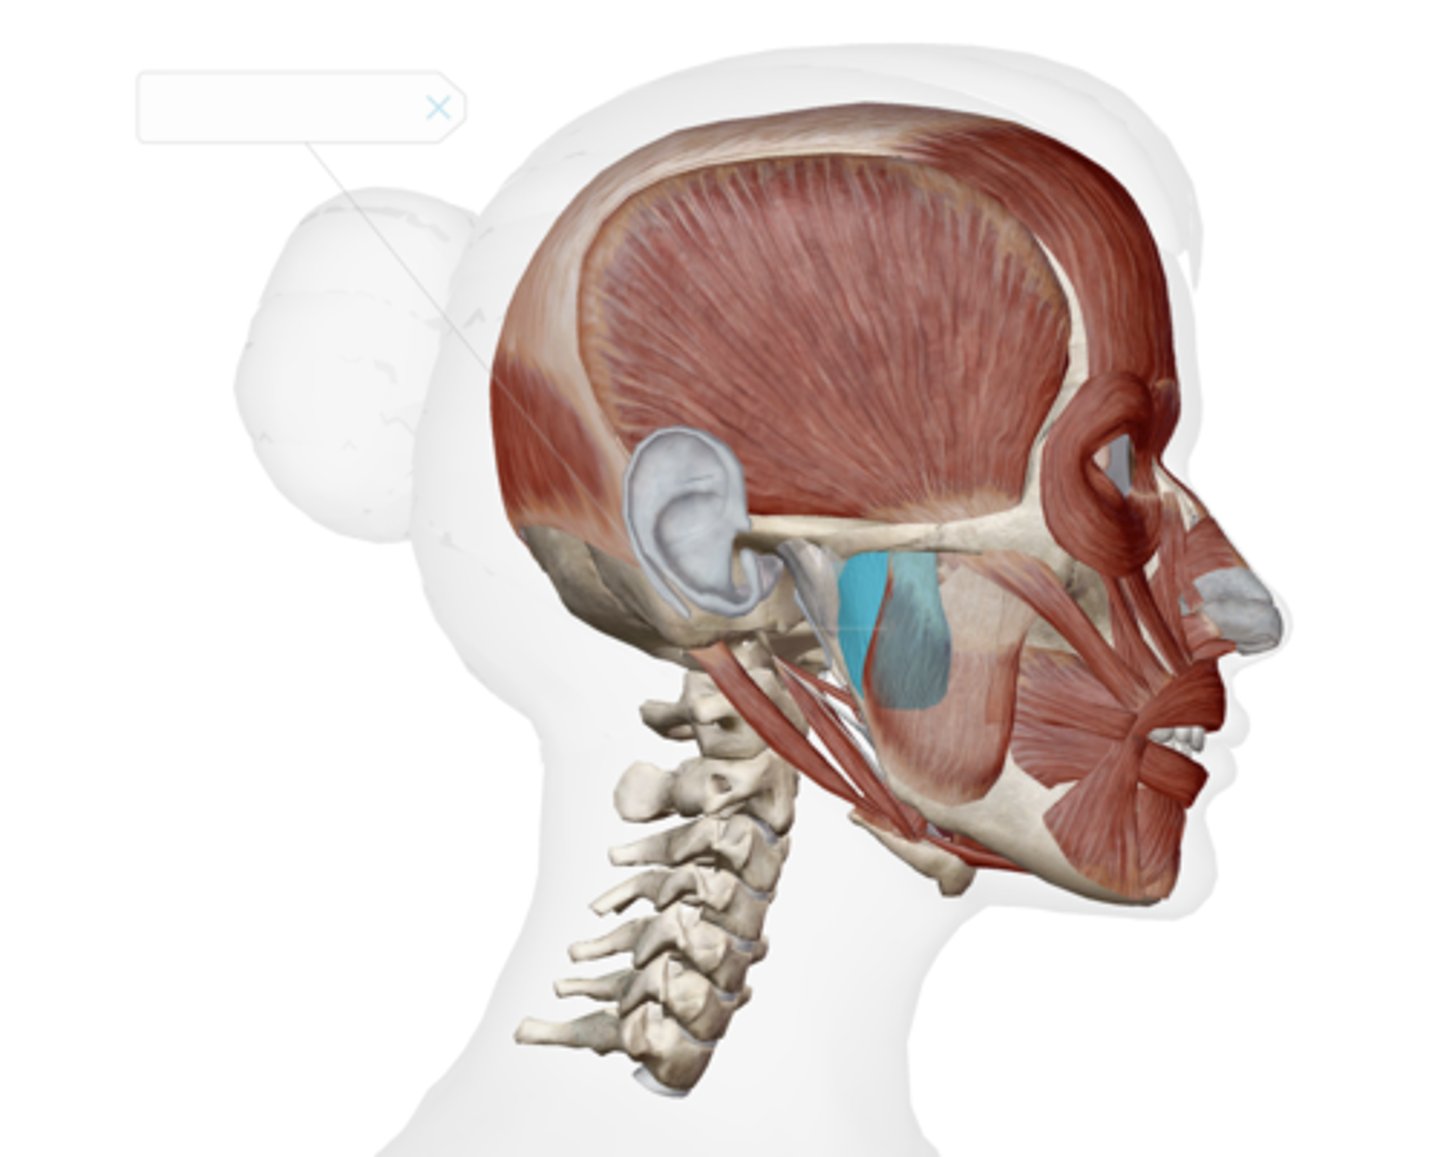

Superficial masseter

Deep masseter

Temporalis